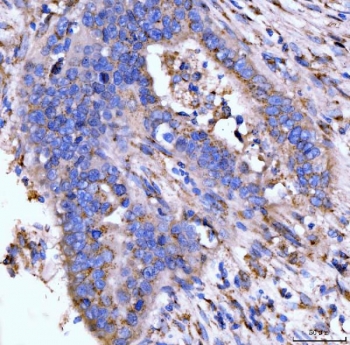

IHC staining of FFPE human appendiceal adenocarcinoma tissue with Giantin antibody. HIER: boil tissue sections in pH8 EDTA for 20 min and allow to cool before testing.